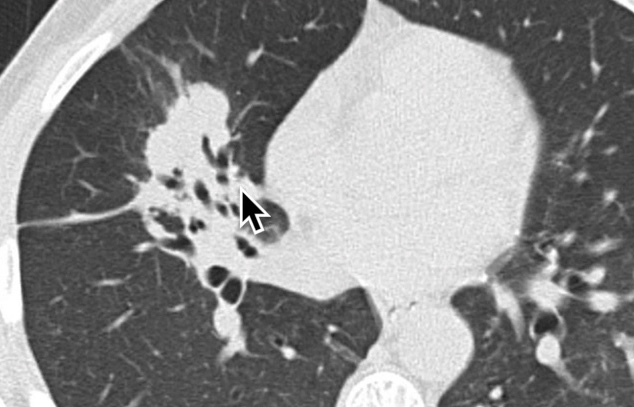

Lymphome Pulmonaire Primaire

- Rare par rapport au secondaire

- Lymphome primaire = sans dissemination extra-thoracique durant 3 mois après Dx

- Masse englobant les structures péribronchovasculaires

- N’oblitère pas complètement les bronches